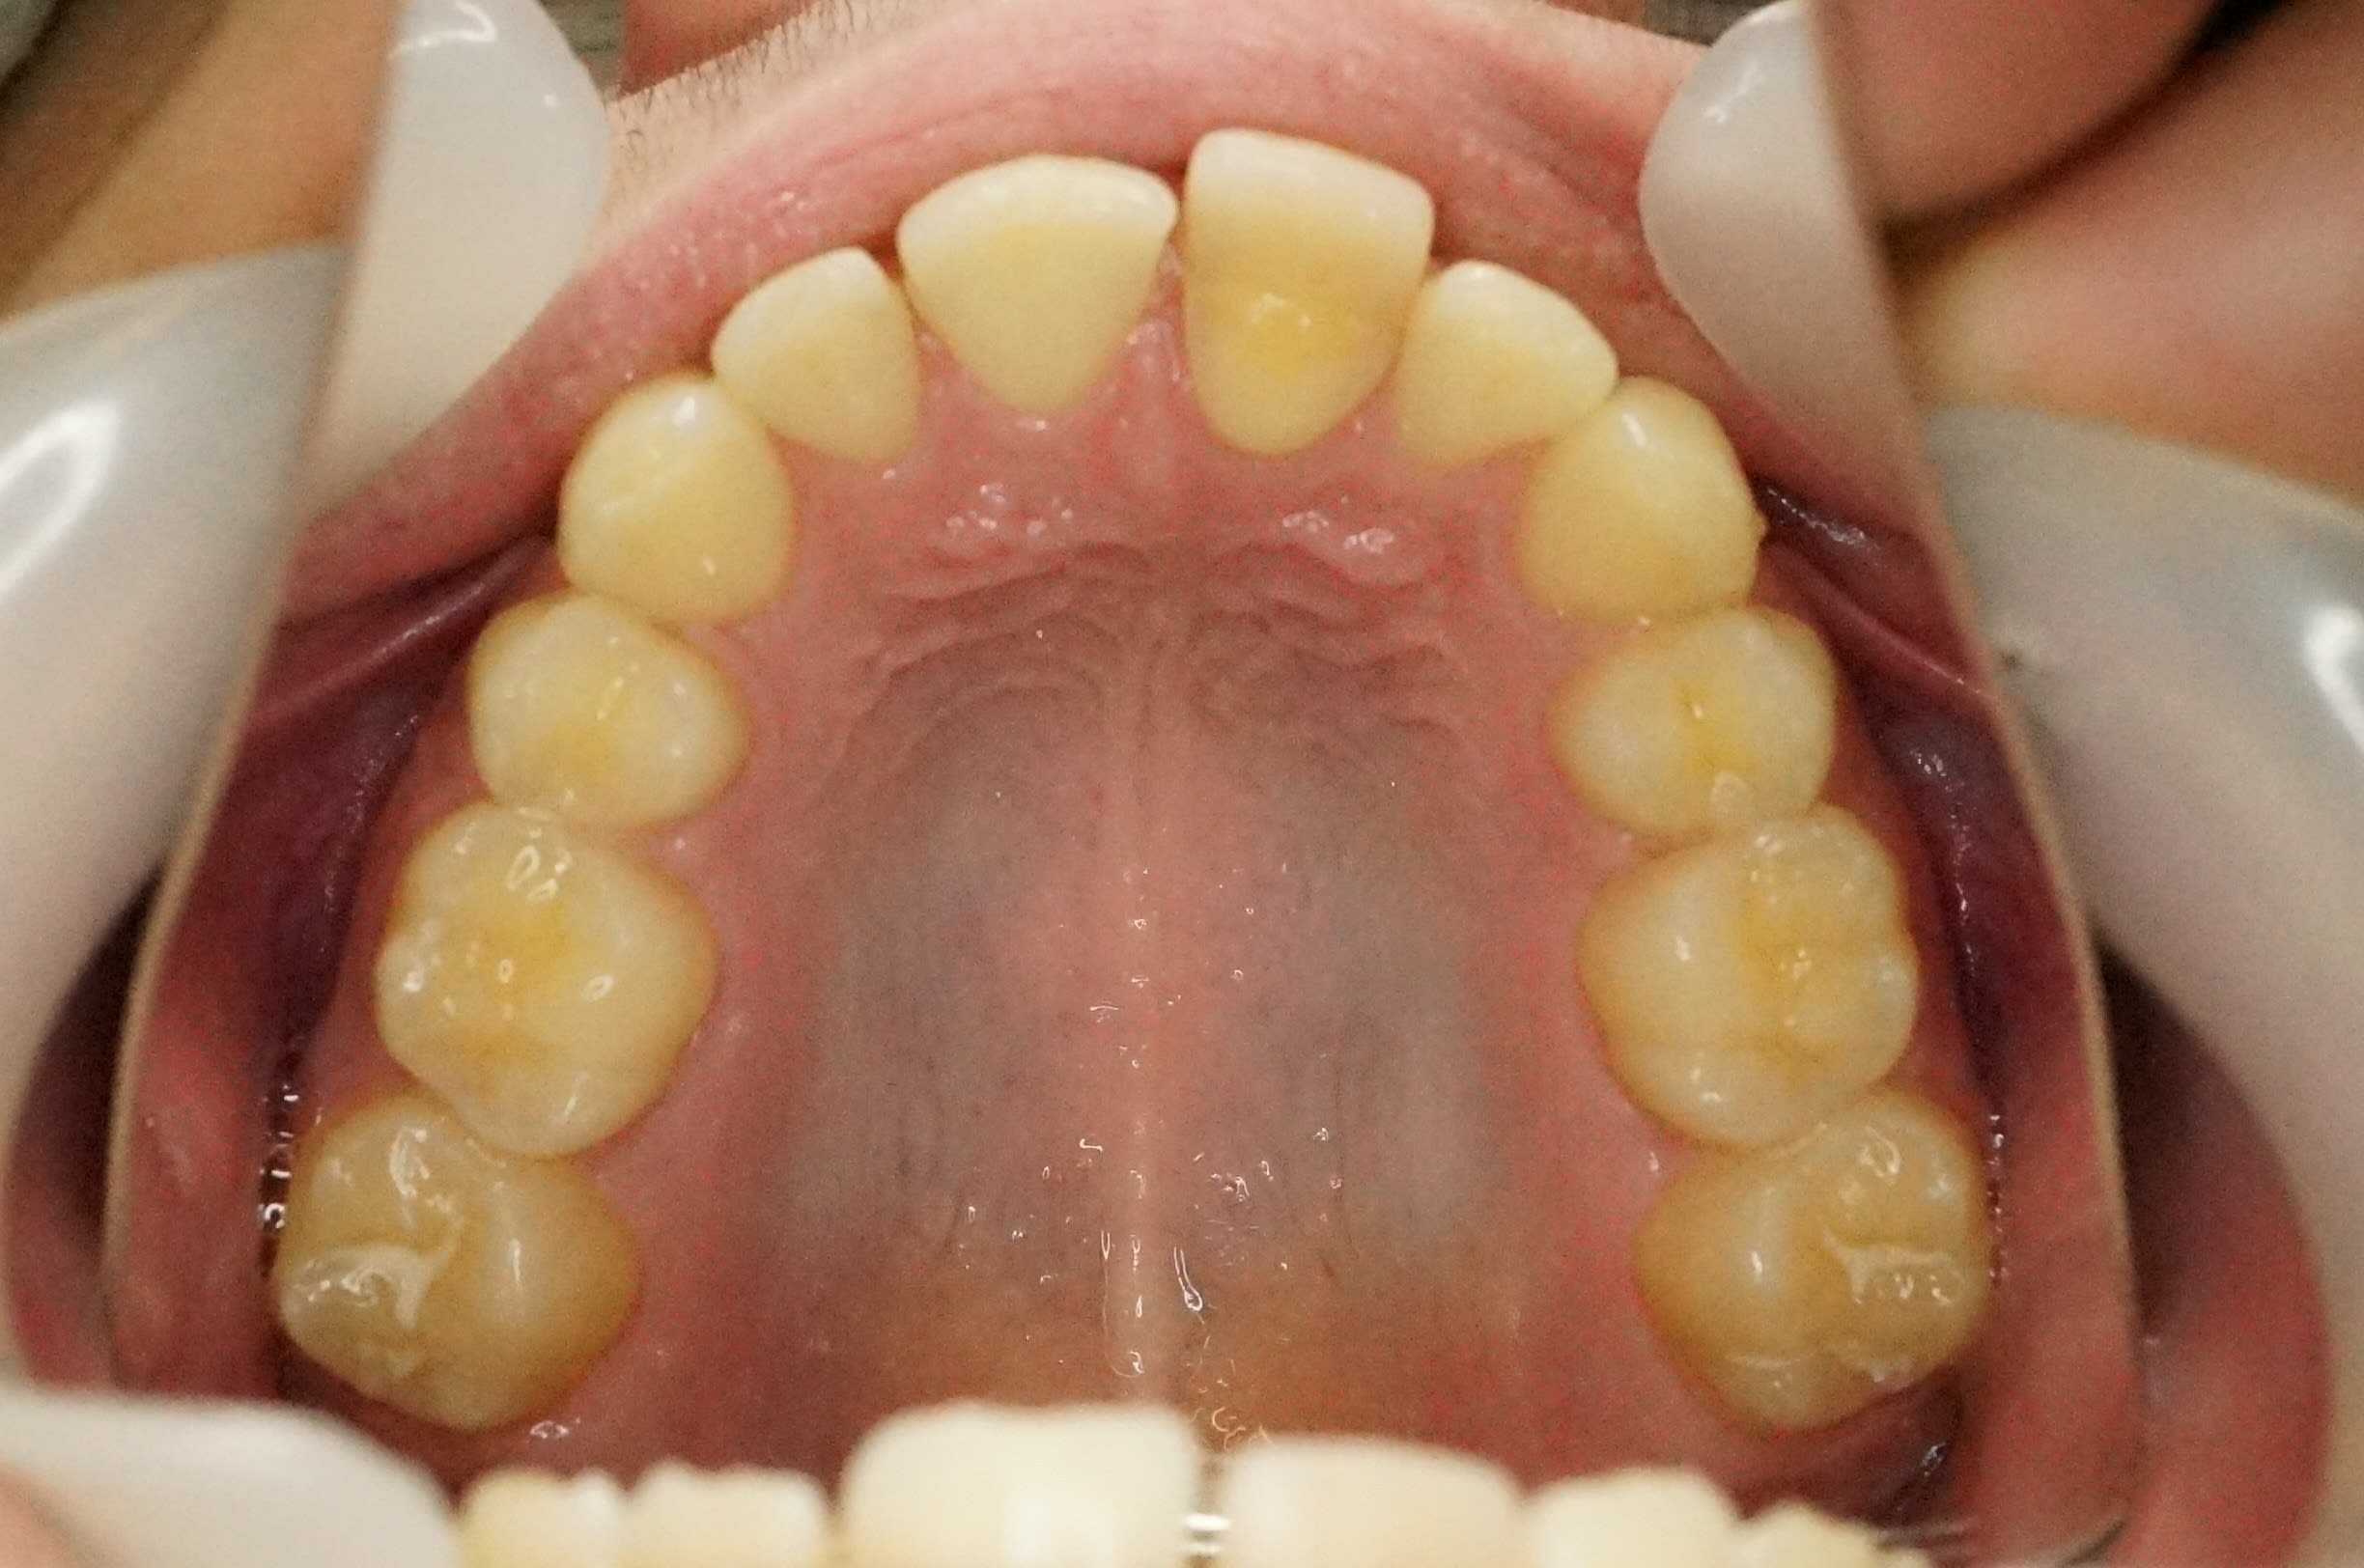

Tu as raison, c'est esthétiquement améliorable de face, cependant son épaisseur la rend trop vestibulaire.

Cela se voit bien ça sur la vue occlusale.